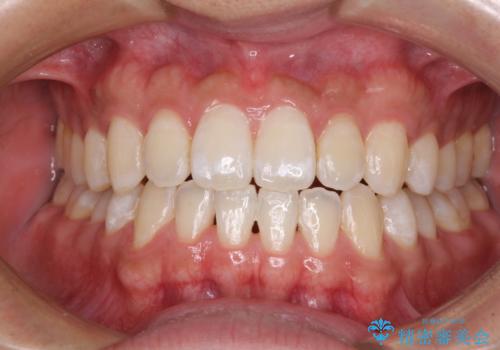

- 上下の前歯の叢生を気にして来院された患者様です。

前歯のみの矯正治療を希望でしたが、上顎臼歯が舌側転位していたため、上顎は全体を、下顎は前歯のみを矯正治療することとしました。

矯正治療は上下全顎を行うことが大前提ですが、費用などの点から、今回は部分矯正を選択することとなりました。

患者様本人は咬みにくさを感じていないようですが、部分矯正は咬み合わせの改善が困難であることが多く、咬みにくさが残ることがあります。